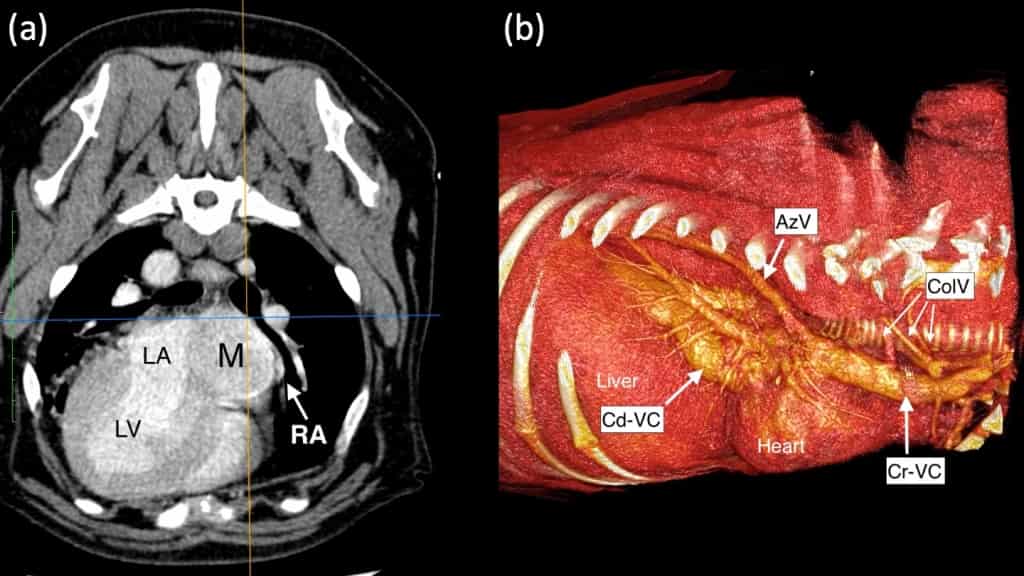

A dog suffering from a complex heart problem was able to return to his grateful owners just 24 hours after a pioneering minimally invasive trans-atrial stent procedure at a leading Wiltshire animal hospital.